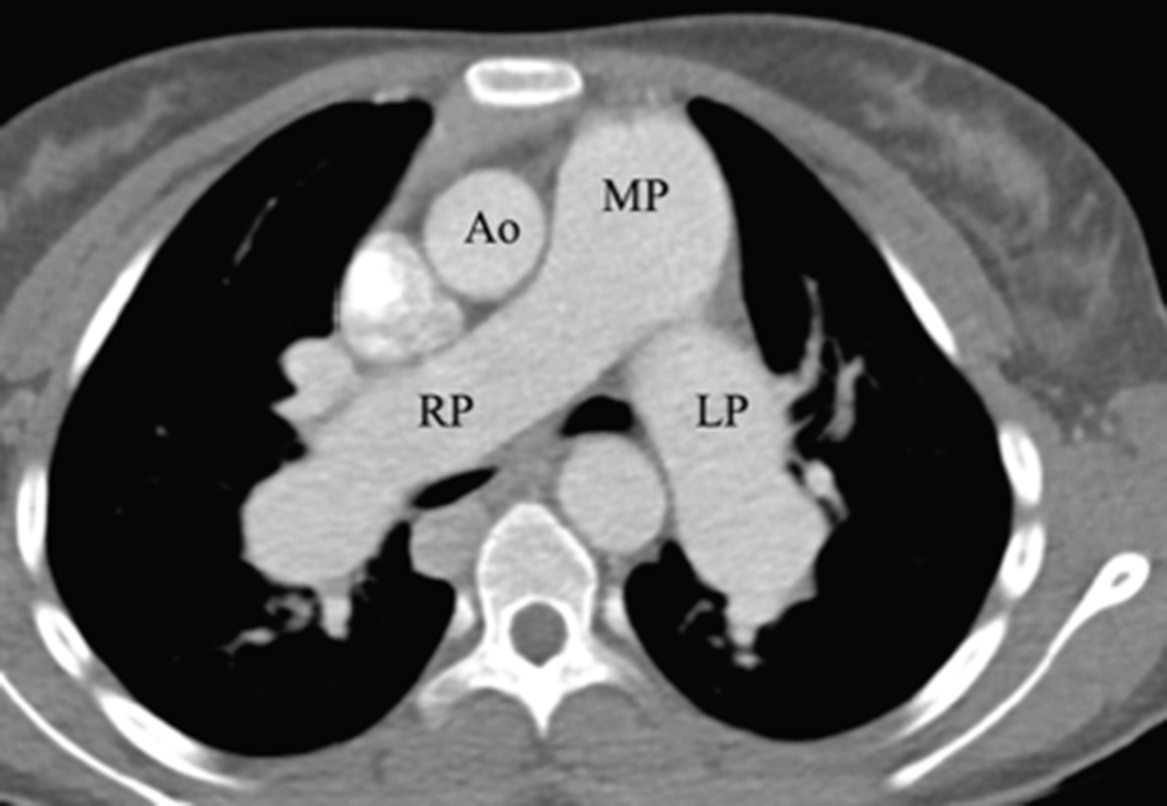

Type 1B Abernathy malformation. (AD) Axial computed tomography images Abernethy Malformation Ct multidetector ct (mdct) is a fast and effective modality for the evaluation of patients with suspected or confirmed portocaval shunts; congenital extrahepatic portosystemic shunt (ceps), also known as abernethy malformation, is a rare condition. abernethy malformations are rare vascular anomalies of the splanchnic venous system. abernethy malformation is diagnosed via noninvasive cross‐sectional imaging such as transthoracic.. Abernethy Malformation Ct.